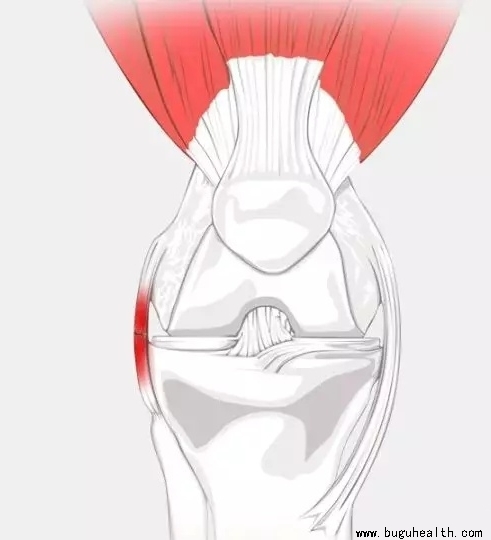

- 股四头肌是人体的大腿肌肉,它位于大腿前侧;股四头肌是人体最大、最有力量的肌肉之一。它是维持膝关节稳定很重要的肌肉;它可以支撑身体的平衡;且具有保护身体能够正常行走或跳跃的作用。所以我们需要重视股四头肌,更要练好它。解剖图示下: .....

- 前交叉韧带重建术后早期最重要的两件事:1.能够完全伸直膝关节;2.激活股四头肌。如果你术后早期就注意这两个问题,这一点都不难,很轻松就可以达到。但如果很不巧,你在早期这两个方面没恢复好的话,后期会非常的麻烦。而且更重要的是,这两者之间是紧密联系的,往往一个不好,另外一个也就不好。.....